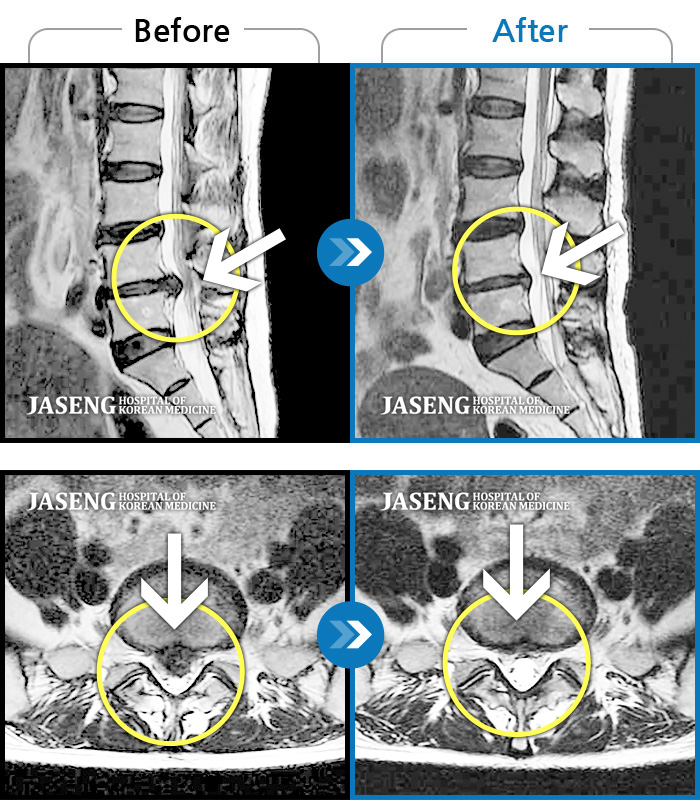

허리디스크

안산 · 김민수 원장

어떤 자세에도 통증이 지속되었다.

촬영시기

2018.10.25 ~ 2024.06.19

2024.07.31